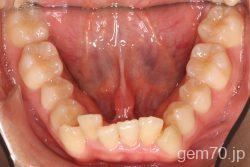

主訴)前歯のかみ合わせが深い

診断)過蓋咬合

使用装置)マルチブラケット装置(セラミックブラケット)

治療方法)4|4/4|4

治療期間) 2年8ヵ月 通院回数 32回